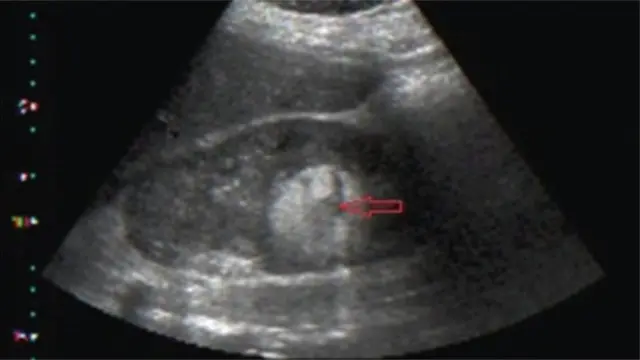

Iwadii imọ ijinlẹ kan ti fi han pe obinrin mẹta ninu mẹwaa, ti ọjọ ori wọn wa laarin ọdun mẹẹdọgbọn si ọgbọn ọdun, lo ma n ni oyun iju ni Naijiria.

Bi oyun iju naa ba ṣe tobi to, iye to jẹ, ati ibi to wa ninu ile ọmọ, ni yoo sọ ami ti obinrin yoo ri.

Ṣugbọn Dokita Brown sọ pe ọpọlọpọ obinrin to ni oyun iju kii ri ami kankan.